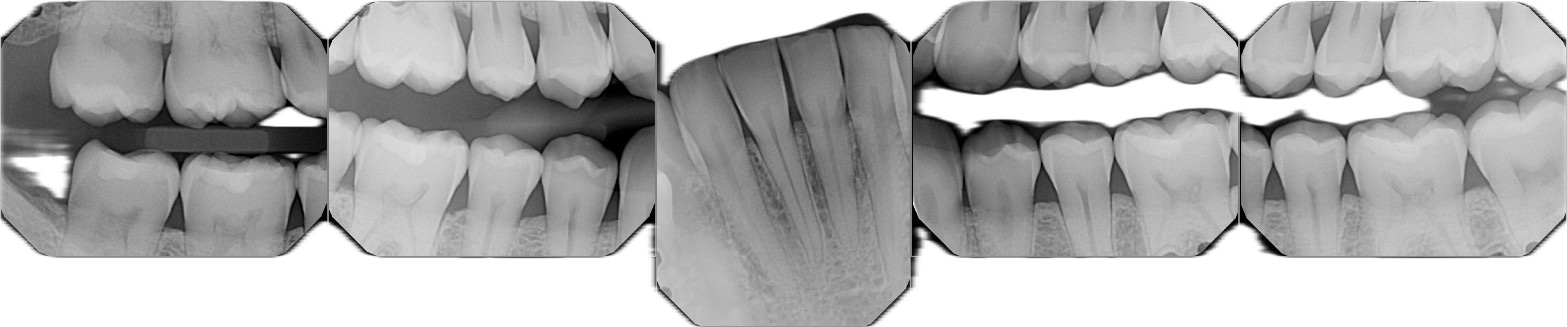

For people on plant-based diets, the types of foods consumed—rich in fruits, vegetables, and fibers—can boost saliva production and encourage the growth of beneficial bacteria. This microbiome shift could potentially help reduce plaque buildup and lower the risk of cavities, gum disease, and even bad breath. By contrast, diets high in animal products often contribute to higher acidity in the mouth, which can damage enamel and promote the growth of harmful bacteria.

This brings up an interesting question: Are we even meant to eat meat? Given the overwhelming dental health benefits of a vegetarian diet—especially when looking at the example of someone in their late 30s without a cavity versus meat-eating relatives with serious dental issues—one might argue that a plant-based diet could be more beneficial for your teeth than any toothpaste on the market.